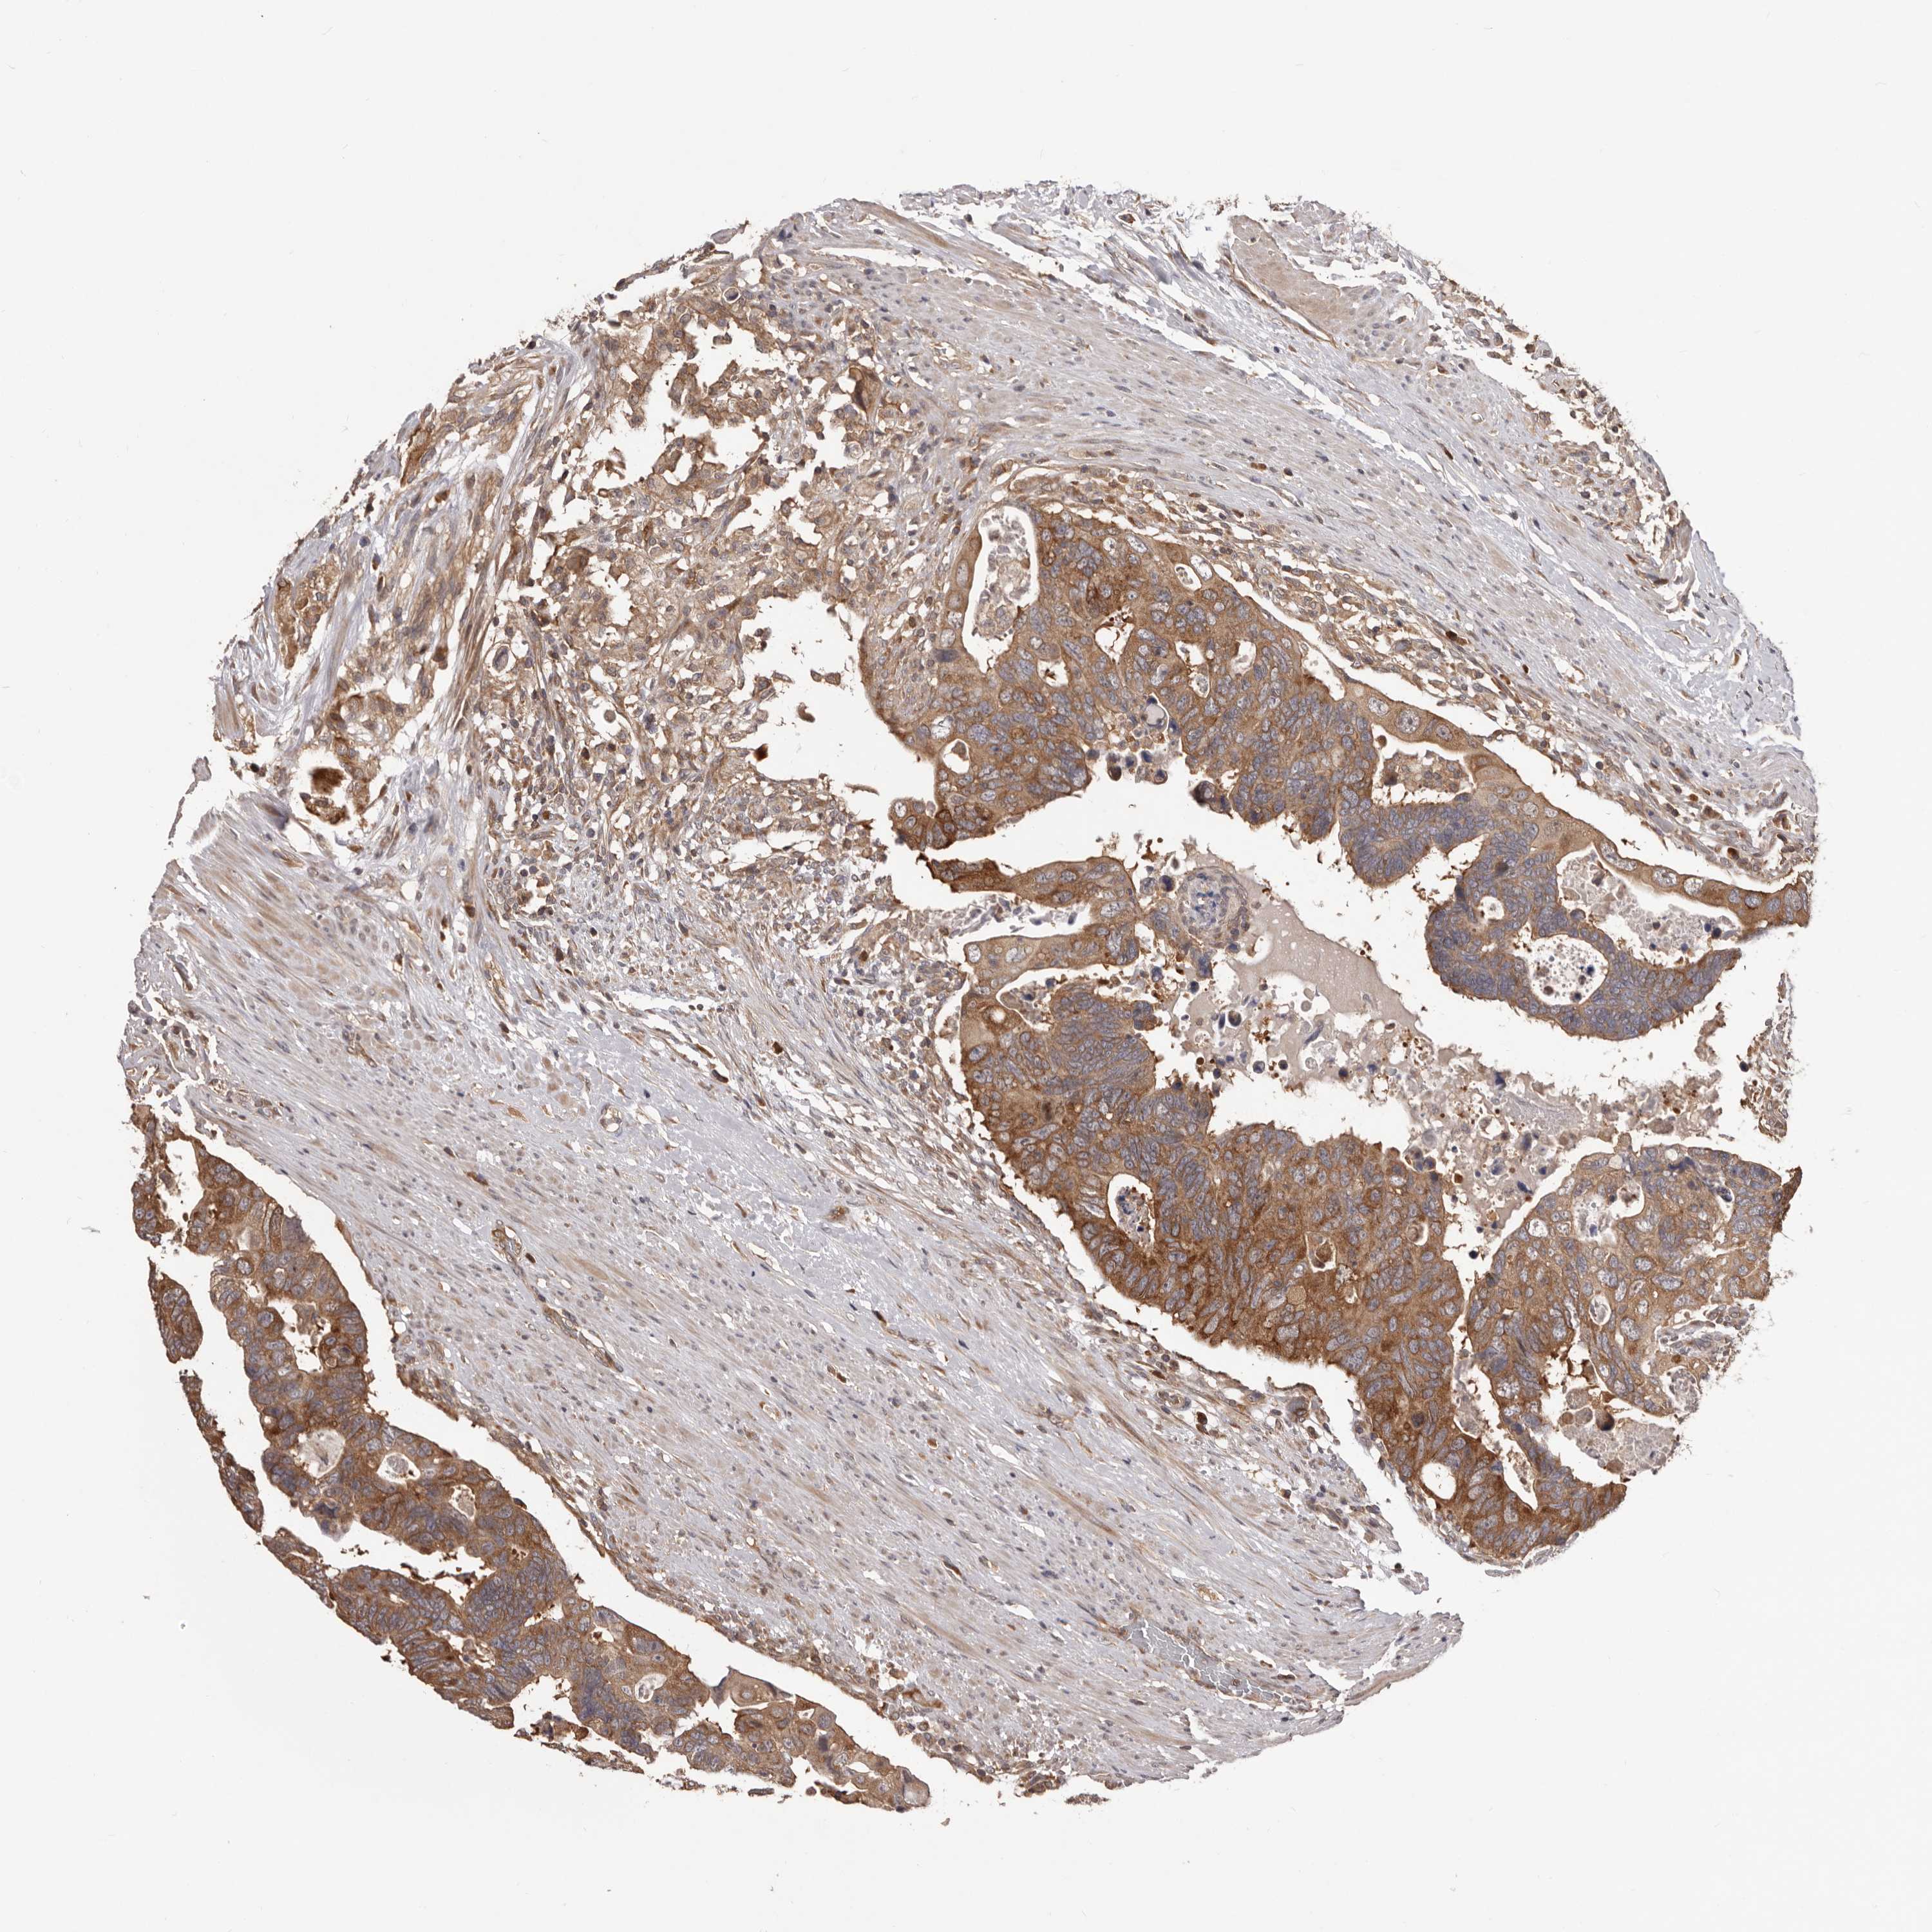

CANCER COLORECTAL CANCER Show tissue menu

Colorectal cancer

Human cancer

Colon adenocarcinoma